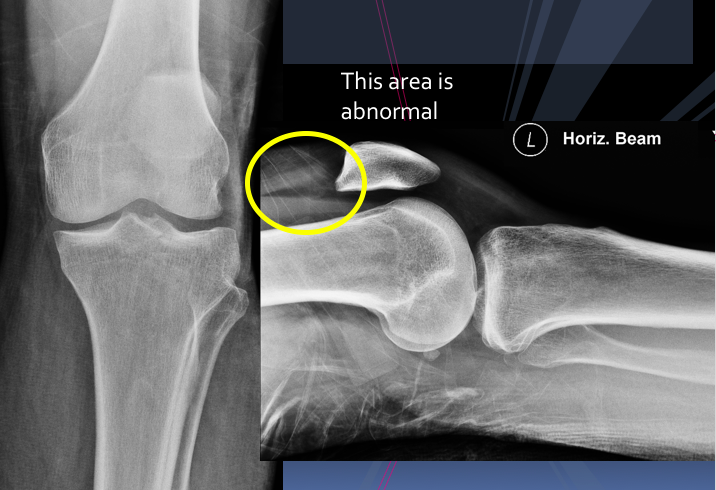

A 30 year old man presented to the ED with left knee pain after a cycling accident.

On examination there was no deformity, but it was painful for him to weight-bear. Movements of his knee were painful, and this limited his movements.

What is a lipohemarthrosis?

Results from an intra-articular fracture with escape of fat and blood from the bone marrow into the joint, and is most frequently seen in the knee.